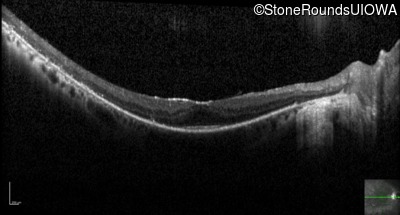

Optical Coherence Tomography - Right - 20/25 -2 sc

Exemplar / OCT Stack

OCT Stack